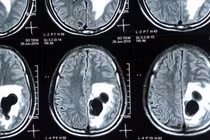

Tiếp nhận người bệnh tại Trung tâm Đột quỵ, các bác sĩ đã nhanh chóng phán đoán và theo dõi đột quỵ não, đánh giá tình trạng, xem phim chụp của tuyến huyện và sử dụng biện pháp tiêu huyết khối. Tuy nhiên, cải thiện của người bệnh chậm, bác sĩ chỉ định chụp CT sọ não kết hợp với ứng dụng hệ thống trí tuệ nhân tạo Rapid.

"Định lượng được tổn thương của não trên hình ảnh của trí tuệ nhân tạo cho thấy vùng não chết có thể tích rất nhỏ, trong khi đó, vùng não có nguy cơ tổn thương rộng. Do đó, bác sĩ quyết định tái thông mạch cứu vùng não có nguy cơ bị tổn thương hoặc có nguy cơ chết mặc dù đã quá giờ vàng", bác sĩ Lục cho hay.

Hệ thống trí tuệ nhân tạo Rapid giúp lượng hóa được các tổn thương của não, từ đó giúp bác sĩ có cơ sở vững chắc để đưa ra quyết định tái thông mạch cho người bệnh đặc biệt là những người đến muộn sau 6-24 giờ. Sau 3 ngày điều trị, sức khỏe của bà Hợp cải thiện rõ rệt, đã đi lại được và giao tiếp trở lại.